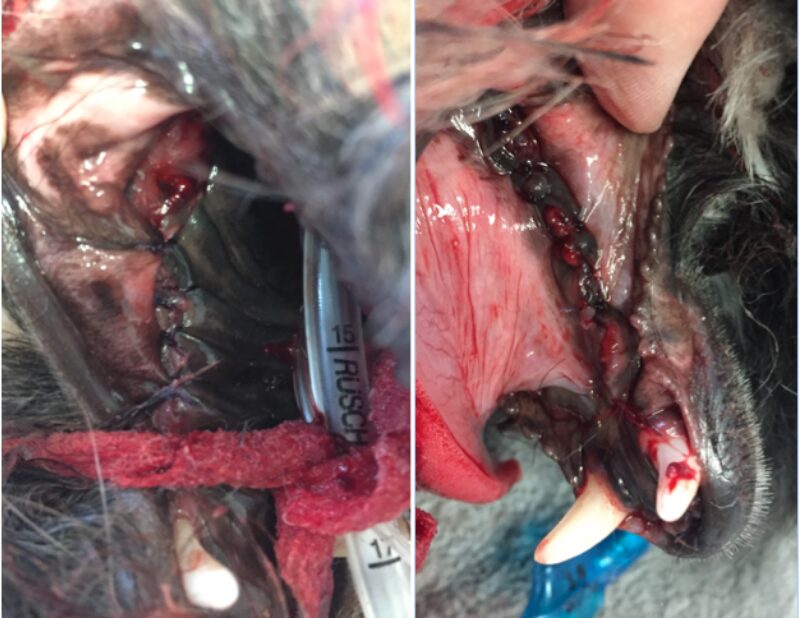

Natürlich versuchen wir immer so viele Zähne wie möglich zu erhalten. Eine Füllung der betroffenen Zähne, hätte die Entzündung nicht eindämmen können und eine zusätzliche Wurzelspitzenresektion wäre vonnöten gewesen. Da jedoch fast jeder einzelne Zahn betroffen war und der Kiefer sowieso schon sehr wenig Halt besaß, wurde auf eine zusätzliche Traumatisierung durch das Aufbohren des Kiefers verzichtet. Daher war der Erhalt der Zähne in diesem Fall nicht möglich. Hätten wir die Zähne drin gelassen, hätte sich der Kieferknochen nicht erholen können und wäre sicher demnächst gebrochen.

Es ist in so einer Situation auch durchaus möglich, dass der Kiefer intra OP frakturiert sobald der Zahn extrahiert wurde und dann kein Halt mehr besteht. Da jedoch der Zahn auch die Ursache der Entzündung ist, blieb keine andere Wahl, als alle Zähne mit der größtmöglichen Vorsicht zu extrahieren. Glücklicherweise blieb der Kiefer stabil und es musste keine Osteosynthese vorgenommen werden.

Die Wunden wurden alle sorgfältig kürretiert (dabei wurden mit einem scharfen Löffel Gewebereste und Schmutz entfernt), gespült und das Zahnfleisch in Einzelheften vernäht. Das Nahtmaterial hierfür sollte resorbierbar, monofil und mit atraumatischer Nadel sein, damit es das empfindliche Zahnfleisch so wenig wie möglich verletzt.